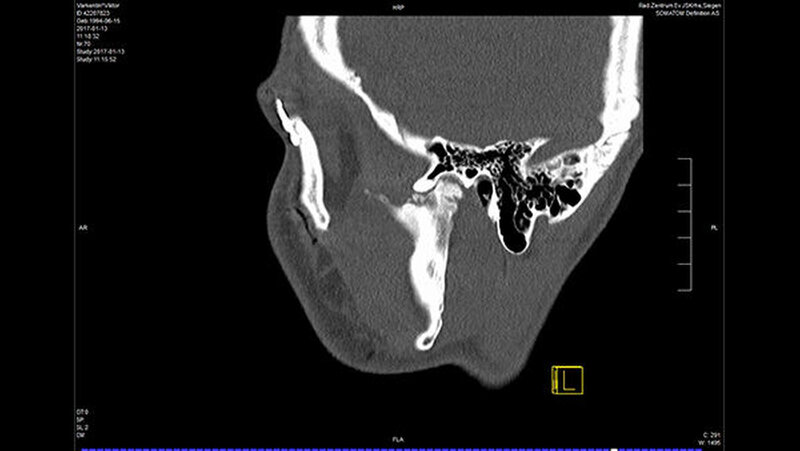

In der Folge entwickelte sich binnen fünf Monaten eine absolute Mundöffnungsbehinderung. Die SKD betrug null Millimeter. Passend zur klinischen Symptomatik zeigten sich radiologisch die Zeichen einer knöchernen Ankylose der Kiefergelenke beidseits Typ III nach Sawhney [1986] (Abbildung 1a-d).

Dem Patienten wurde der totale Gelenkersatz beidseits mit auf der Basis der gewonnenen CT-Daten individuell erstellten Fossa-Komponenten aus einem speziellen Kunststoff (Ultra High Molecular Weight Polyethylene) und individuellen Gelenkkopfprothesen aus einer titanbeschichteten Chrom-Kobalt-Legierung vorgeschlagen (Biomet Microfixation Inc., Vertrieb Zimmer Biomet Deutschland GmbH). Der Patient und seine Angehörigen wurden in intensiven Gesprächen über die Vorteile und Risiken des Eingriffs aufgeklärt.

Nach Akzeptanz des Behandlungsplans wurden beidseits die TEPs (Totalendoprothesen) über jeweils einen präaurikulären und einen retromandibulären Zugang implantiert. Diese Prothesen wurden mit Schrauben mit exakt am CT-Datensatz definierten Schraubenlängen fixiert. Bei der Planung der Schraubenpositionierung wurde auch der Verlauf N. alveolaris inferior berücksichtigt und der Nerv geschont.